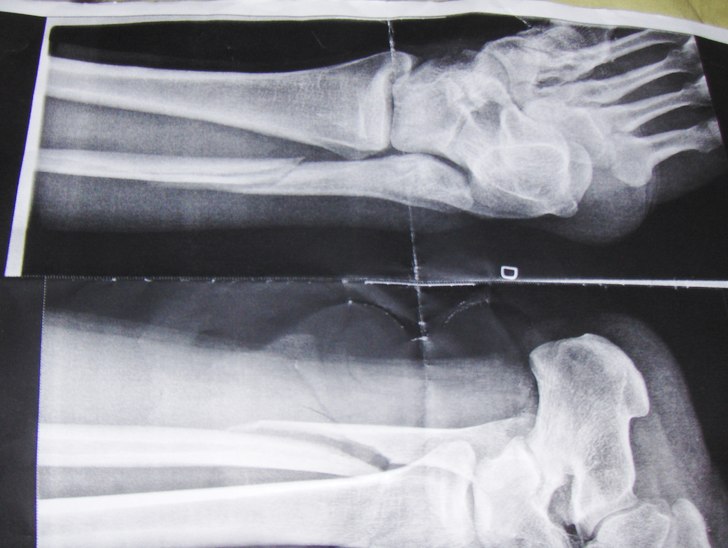

Anledningen till att jag inte blev en bätre skateboardåkare i sommar men fick större självinsikt om mina begränsningar på studsmatta...

- Kategori: Studsmatta

- Fotograf: röntgenläkare nus

- Åkare: Anders mangs

- Skidort: NUS